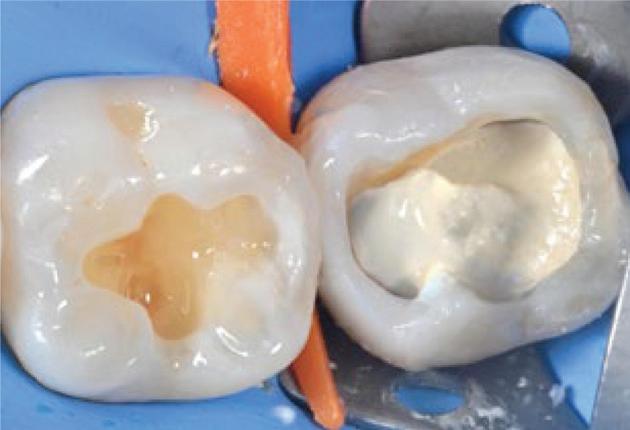

Biodentine™ in Bio-Bulk Fill procedure as a core material for indirect restoration

The Ivoclar Group is launching Tetric® plus, a new simplified composite specially designed to set new standards in universal composites. Tetric plus takes its name from the Greek prefix “tetra”, meaning “four” and this number is central to its key product features. It incorporates four essential elements: simplified shade matching with just 4 shades, increments of up to 4mm for greater efficiency, versatile application options in all 4 quadrants and an optimised 4-filler technology for excellent handling and aesthetic results.

Tetric plus revolutionises shade selection in dentistry, allowing for easy shade matching with its innovative colour cloud concept. Just 4 shades cover the entire spectrum of the classical VITA shades. Thanks to its exceptional shade adaptation, Tetric plus creates an outstanding chameleon effect: In its cured state, the material absorbs and scatters light in a way that closely mimics natural tooth structure, allowing it to blend almost seamlessly with the surrounding tooth structure. This high level of adaptation is achieved through the perfect combination of monomers, fillers and pigments.

Another remarkable feature of Tetric plus is its ability to accommodate variable layer thicknesses ranging from 0.1 to 4mm, allowing for greater flexibility while also reducing material consumption. Another notable advantage is its reliable curing time of just 3 seconds,1 that allows for a fast and easy application. These short curing times streamline workflows, minimise interruptions for dentists and enhance treatment efficiency. By enabling faster and more efficient restorations, Tetric plus not only saves valuable time but also improves the overall patient experience.

Tetric plus is a simplified universal composite that is suitable for all cavity classes, from Class I to V. With just one product, dentists can treat a wide range of indications in all 4 quadrants, significantly reducing material consumption and streamlining the workflow. For maximum handling convenience, Tetric plus is available in two viscosities: sculptable and flowable.

The quality of Tetric plus is defined by its innovative 4-filler technology, which integrates a combination of nano-

and micro-particles to deliver outstanding mechanical properties. Tetric plus ensures reliable curing for layers of up to 4mm while offering high radiopacity to facilitate accurate detection during diagnosis. The mechanical properties include high flexural strength (133 MPa), high compressive strength along with low wear and low shrinkage stress, reducing the risk of marginal gaps.

Tetric plus is more than just another composite: it is designed to simplify the daily workflow of dentists and optimise their treatment efficiency. With easy shade selection and short curing times, dentists can focus entirely on patient care, while delivering efficient and high-quality work. In summary, Tetric plus combines 4 shades with 4mm layer thicknesses, universal applicability in all 4 quadrants and an innovative 4-filler technology, making it the ideal solution for the demands of modern dentistry.